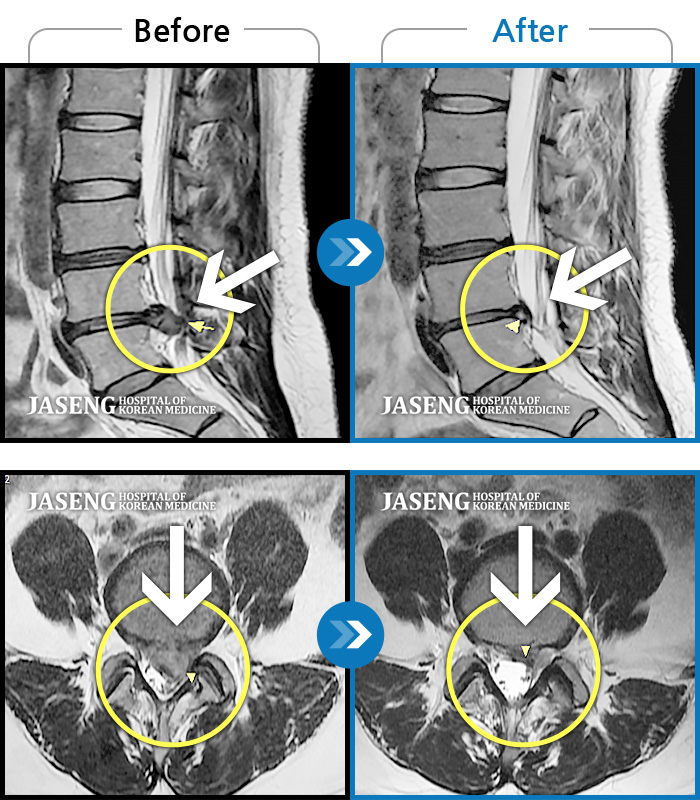

저는 교통사고 후유증과 운동부족,잘못된 자세등으로 간혹 허리가 아팠습니다.. 근데 최근 몇일간 무리한후에 허리가 아프고 왼쪽 하지방사통과 저린감이 너무 심하여 밤에 잠도 제대로 들기 어려울 정도 였습니다...MRI를 찍으니 디스크라고 하더라구요..ㅠ..ㅠ 예상은 하고 있었지만 20대후반에 디스크라니...좌절감과

우울감이 심하였습니다.. 무조건 수술은 안하리라는 생각에 원장님을 찾아뵈었습니다..저한테는 어떻게보면 행운이였나봅니다...

앞으로 치료계획에 대해 상세히 설명해주시며 믿음과 희망을 주셨습니다 ..마음이 한결 가벼워 졌습니다..

추나, 침, 약침, 물리치료, 약물(한약)요법을 병행하며 현재 2주가 조금 지났는데...저도 놀랄정도로 왼쪽 하지방사통은 거의 없어졌어요..감동감동 ㅠ..ㅠ

치료에 대해 믿음이 있었지만 이렇게 빨리 회복이 될지는 저도 놀랐습니다...